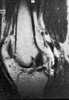

Idiopathic popliteal cyst